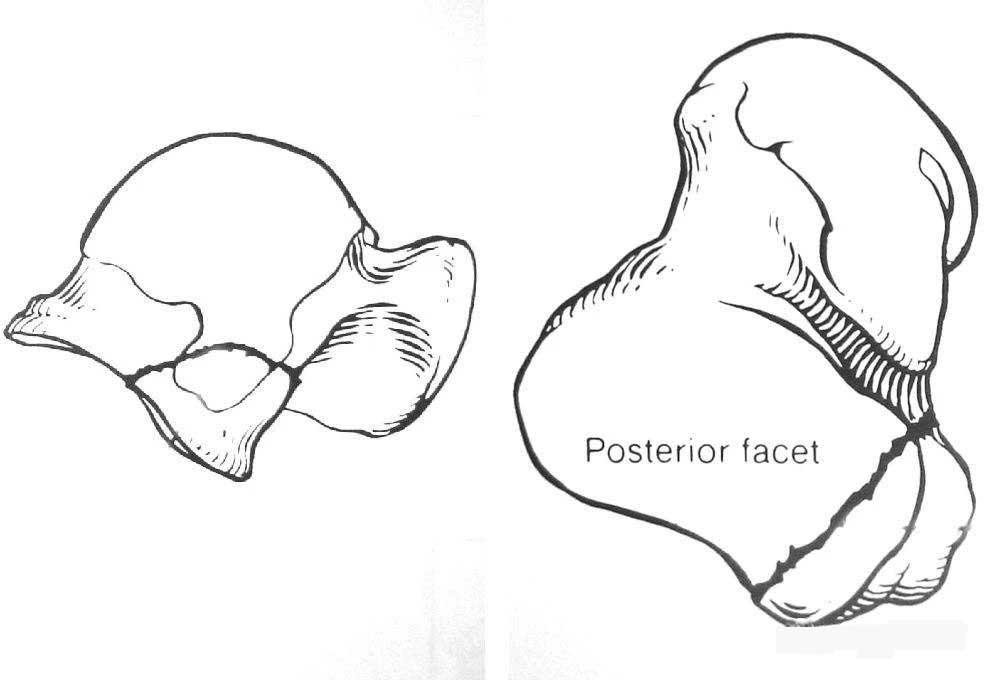

El astrágalo se encuentra en la parte superior del arco del pie, dentro del punto del tobillo. Como bisagra que conecta la pierna y el pie, las articulaciones del astrágalo tibial y subastragalino proporcionan la movilidad principal del pie trasero. El astrágalo es el segundo hueso tarsal más grande del cuerpo humano. Aproximadamente dos tercios de su superficie están cubiertos por cartílago articular. Es el único hueso del cuerpo sin unión tendinosa. Su estabilidad se mantiene principalmente por la estructura ósea circundante, la articulación tejido de la cápsula y del ligamento. La cabeza del astrágalo está articulada a la parte anterior del escafoides y está sostenida por el ligamento del escafoides (resorte) del calcáneo. La superficie inferior del astrágalo tiene 3 superficies articulares (anterior, media y posterior) conectadas a la superficie superior del calcáneo. Hay un tubo tarsiano entre la superficie superior del calcáneo y la superficie inferior del astrágalo, que se abre lateralmente para formar el seno del tarso.